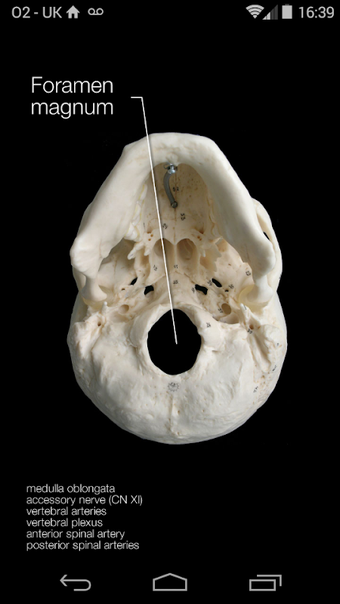

Skull Osteology, kafatasının kemik özelliklerine kapsamlı bir rehber sunan Dr. Samuel Webster PhD tarafından geliştirilmiş bir Android uygulamasıdır. Uygulama, tıp öğrencileri de dahil olmak üzere anatomiyi öğrenen öğrencilere kemiklerin, sutürlerin ve foramenların öğrenilmesine ve tekrar edilmesine yardımcı olmak için tasarlanmıştır. Uygulama, kemiklerin, sutürlerin ve foramenların dokunarak etiketlenmiş etkileşimli fotoğraflarını içerir. Kemikler renkler ve isimlerle etiketlenirken, sutürler adlandırılır ve foramen etiketleri içinden geçen yapıların listelerini içerir.

Uygulama kullanıcı dostudur ve öğrencilerin kafatasının kemik özelliklerini öğrenmeleri ve tekrar etmeleri için mükemmel bir yoldur. Fotoğraflar net ve detaylıdır ve dokunarak etiketleme, kafatasının farklı parçalarını tanımlamayı kolaylaştırır. Uygulama ücretsizdir ve anatomiyi öğrenen öğrenciler için harika bir kaynaktır.